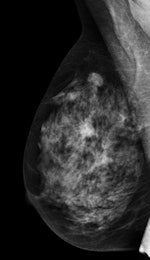

Mean of the coefficients of variations (COVs) of all 15 image quality indexes for each system. Data are grouped and colored by system brand. The horizontal line represents 5% variability. All images courtesy of Dr. Gisella Gennaro and European Radiology."This retrospective analysis from the large image dataset produced by 25 digital mammography units and collected within a two-year regional project has demonstrated that, overall, reproducibility of image quality produced by full-field digital mammography systems is excellent," noted lead author Dr. Gisella Gennaro, a medical physicist from the Veneto Institute of Oncology in Padua, and colleagues (European Radiology, 27 January 2017).